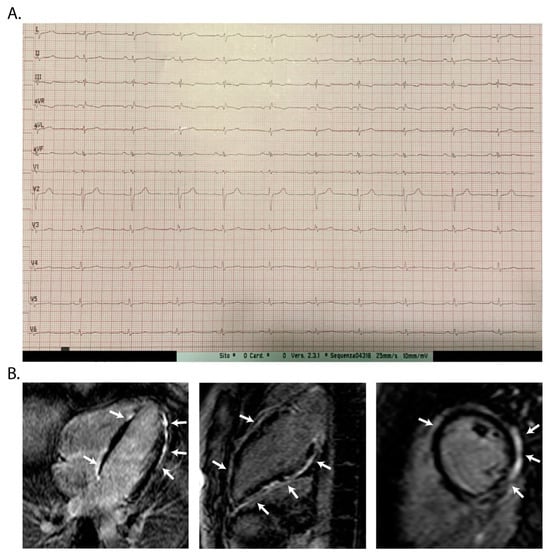

2.4. Twelve-Lead Electrocardiography

2.2. Cardiac Magnetic Resonance